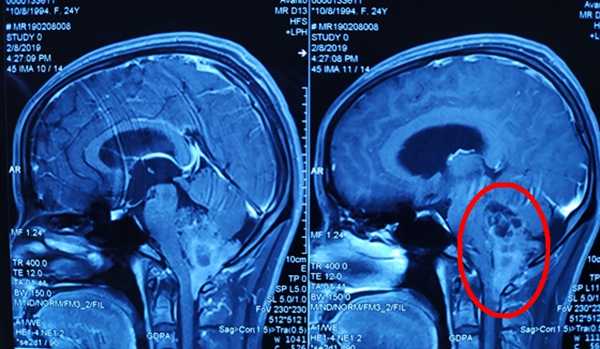

到达常德后,袁贤瑞教授查看病人并阅片后考虑: 患者为四脑室起源肿瘤,肿瘤巨大,向上生长接近中脑导水管下口,向下穿越枕骨大孔侵袭至寰椎下缘,向前压迫脑桥、延髓及部分颈髓,并包绕左侧后组颅神经、面神经等,向后累及双侧小脑扁桃体及小脑蚓部等,已导致小脑扁桃体下疝、梗阻性脑积水的形成。“情况危急,患者随时可能病情加重,出现枕骨大孔疝危及生命,必须尽早手术”,袁教授安排好术前相关事宜,与家属商议后决定初五早上为患者手术。

整个手术历时6小时,在保护好脑桥、延髓及小脑等重要功能区域的前提下顺利切除肿瘤,大小约为6.5cm*5.2cm*4.1cm。考虑肿瘤对脑桥、延髓等生命中枢压迫严重,虽然已手术,解除了肿瘤对上述生命中枢的压迫,但因脑干肿胀、血管痉挛、血运回流障碍等综合因素对脑干影响,术后极易导致患者呼吸衰弱、心率不稳、血压下降等呼吸、循环功能障碍,甚至呼吸、循环功能衰竭,严重时可出现呼吸骤停,若抢救不及时,极易出现生命危险。术后王女士立即被送往重症监护室,严密监测生命体征、观察患者呼吸、循环功能,并通过一系列生命支持及相应诊疗措施,病情稳定好转,术后一直未发现呼吸功能下降、循环功能障碍等异常。见王女士病情稳定后,袁贤瑞教授才安心返回长沙。